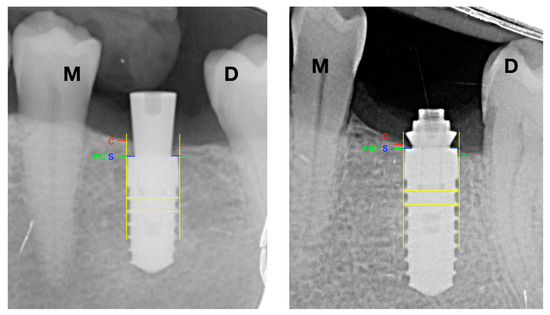

Consequently, all radiographs were calibrated by assessing their possible distortion, using the distance between the threads of the implant body as a known value. All implants were evaluated by drawing vertical lines parallel to the long axis of the implant, taking the implant platform (S) as the starting point, then the mesial and distal crestal bone level of each implant was recorded. Besides cases of presenting bone tissue on the platform, the measurement was from platform to bone crest (C). In addition, in cases where the bone crest (C) was apical to the implant platform, the distance between the platform (S) and the first bone-implant contact (FIC) was measured—see Figure 3.

Negative values (−) were established in case the implant platform was subcrestal and positive values (+) if it was coronal to the bone crest.

For the statistical analysis, the value was obtained using a mean between the mesial and distal values of radiographic bone loss.

Two operators, previously calibrated (BRC and GTG), marked the turns, implant platform (S), bone crest (C), and first bone-implant contact (FIC) and measured the distances between turns, SC, and S-FIC using the ImageJ software (National Institutes of Health, Madison, MD, USA).

Figure 3. Radiographic analysis. S: implant shoulder; C: bone crest; FIC: first bone to implant contact; M: mesial; D: distal; SC distance: marginal bone level at the crest; S-FIC distance: marginal bone level at the implant.